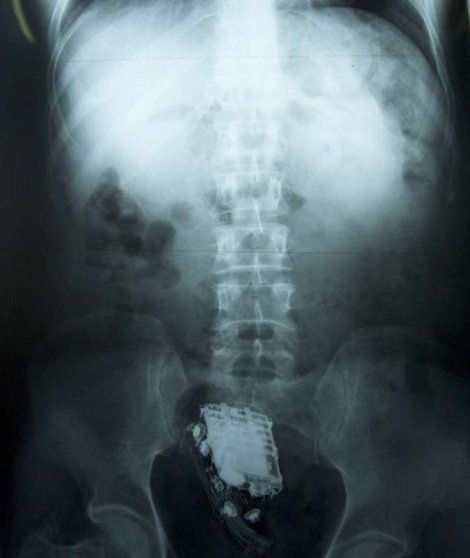

Zatvorenik je odmah odveden u bolnicu, gdje je posle snimanja rendgenom utvrđeno da mu se u anusu nalazi mobilni telefon.

Hirurškom intervencijom mu je telefon uklonjen iz tijela, a muškarac koji je na izdržavanju 10 godišnje kazne zbog krađe, vraćen je nazad u zatvor.